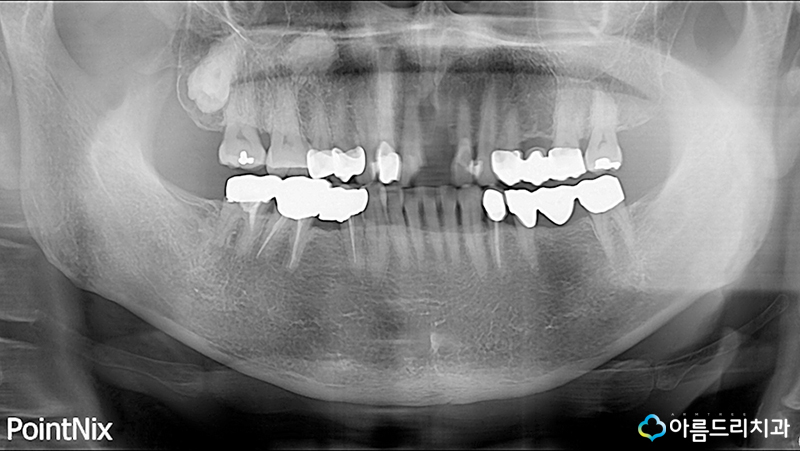

위의 사진은 당시 치아 사진인데요. 우선 어떻게 넘어지셨는지 다른곳은 다치지 않으셨는지 걱정부터 되기 시작했습니다.

환자분은 사고가 난 지점 근처에 있는 치과에 가셨다가 바로 다시 저희 아름드리 치과에 오시게 되었다고 하시는데요.